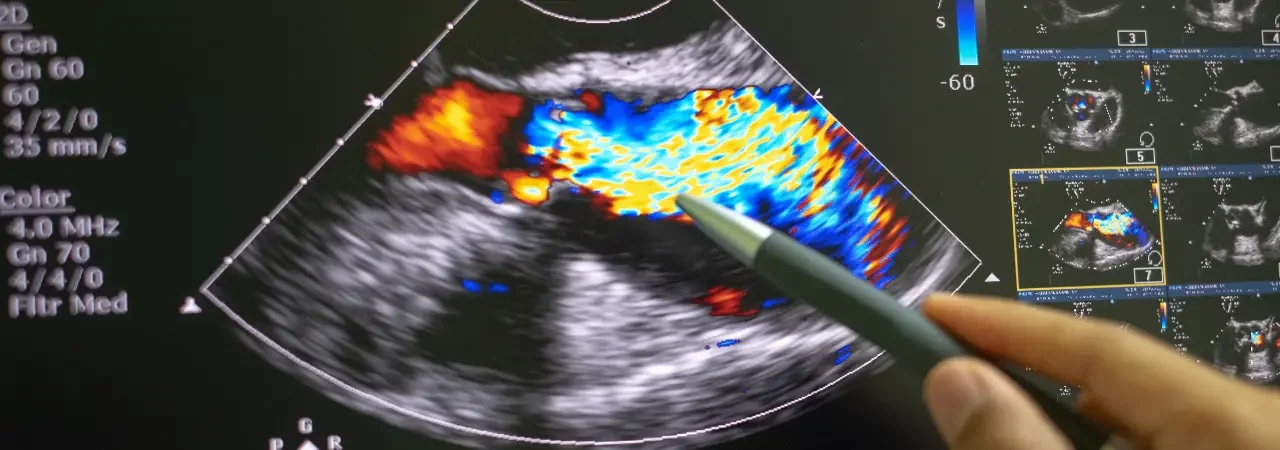

BT anjiyografi ile ölçüm ve anatominin uygunluk analizi

BT anjiyografi, planlamanın bel kemiğidir. Önce centerline üzerinden ölçüm alır, sonra iniş alanlarını ve sızdırmazlık için gerekli kapaklanma uzunluklarını belirleriz. Boyun/landing zone uzunluğu, damar çapları, kavis (tortuozite) ve kalsifikasyonu değerlendirir; buna göre tevar stent greft boyutlandırmasını genellikle %10–20 oversize prensibiyle yaparız. Ayrıca:

- İliak/femoral erişimi çap, kalsifikasyon ve şekil olarak doğrularız.

- Visseral dallar, arkus varyantları ve dallanma mesafelerini işaretleriz.

- Gerektiğinde fenestrasyon/branched seçeneklerini ve hibrit yaklaşımları tartışırız.

Son olarak, anestezi stratejisini (lokal + sedasyon ya da genel) ve kontrast/ışın dozunu optimize eder, adım adım planı yazılı hale getiririz; böylece prosedürde sapma olmadan ilerleriz.